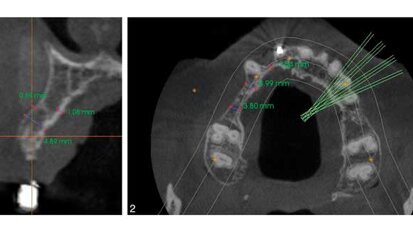

3D imaging: Increasing implant accuracy

Implants are making news on a global scale. According to The Wall Street Journal’s Market Watch, the implant market “is mainly driven by the ...